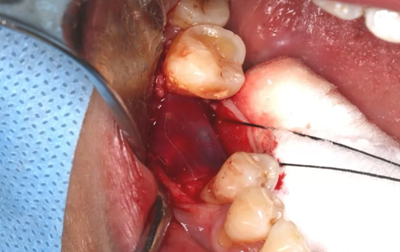

取下攜帶體,旋入封閉螺絲,潛入式愈合。

(攝于2017年4月14日)

組織瓣復(fù)位,常規(guī)間斷縫合。